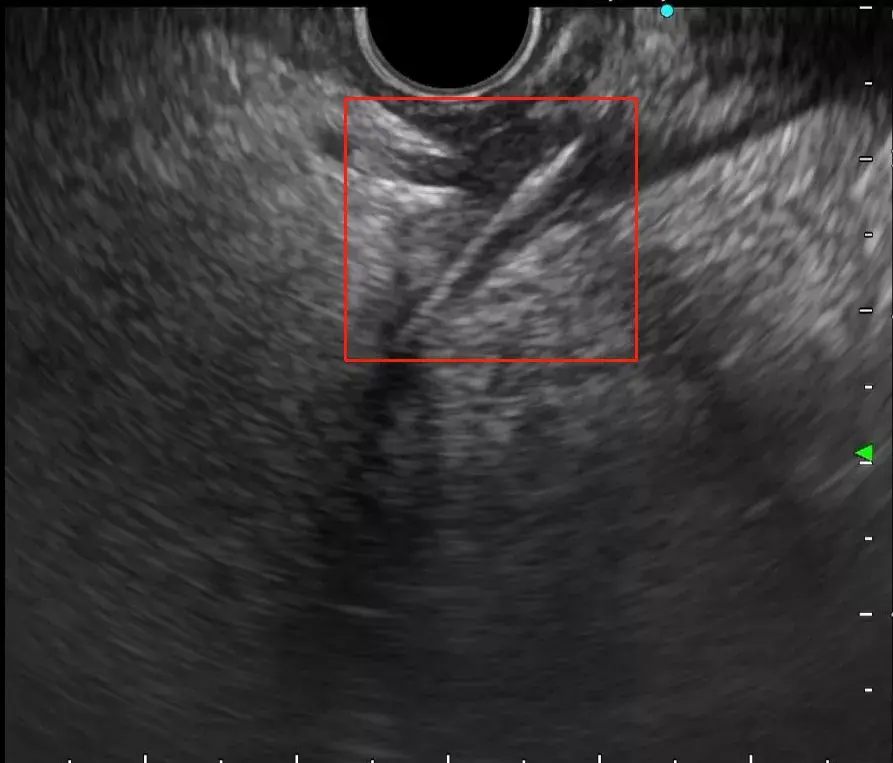

红框里为严叔肚子里的异物

“找到了!”随着一阵欢呼声响起,超声内镜屏幕上清晰地显示出一条约三厘米的高回声异物——真凶初次露出了它狰狞的面目。陈洪潭主任对异物、胰腺以及周边大血管之间的位置进行了仔细地扫查,发现鱼刺和胰腺之间,有一条动脉血管穿过,如果再不及时取出鱼刺,很可能就会穿破动脉血管,造成大出血,那时后果将不堪设想!